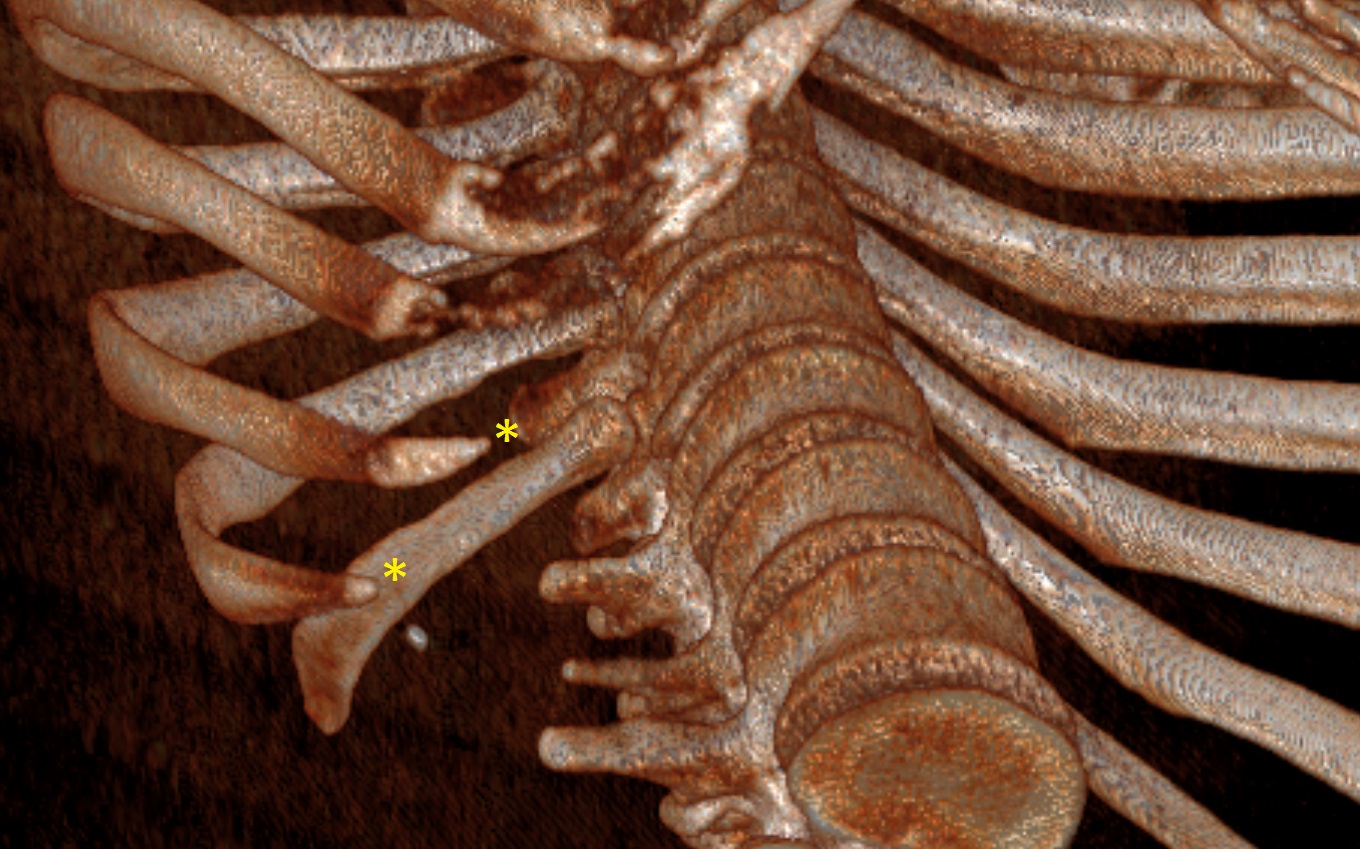

L'instabilità delle giunture costali può portare allo scivolamento delle punte libere delle coste inferiori (Figure 1-2), causando dolore e irritazione dei tessuti circostanti (Figura 3), in particolare del nervo intercostale corrispondente o dei fasci muscolari/tessuti molli adiacenti, generando una condizione di dolore toracico cronico; solitamente la X costa è quella più colpita.

Ricostruzione Tc Torace 3D che mostra le punte costali libere della X-XI costa

costali libere della X-XI costa (fig.1 e fig.2)

Tuttavia, a causa della somiglianza dei sintomi con altre condizioni toraciche, possono essere necessari esami di imaging come radiografie, ecografie, TC o risonanze magnetiche. Le indagini radiologiche mostrano in genere reperti minimamente patologici e non sono dirimenti in senso diagnostico, bensì risultano più utili per escludere patologie sottostanti. La Tc Torace con ricostruzioni tridimensionali (Figure 1-3) può confermare il sospetto clinico ed indirizzare il trattamento.